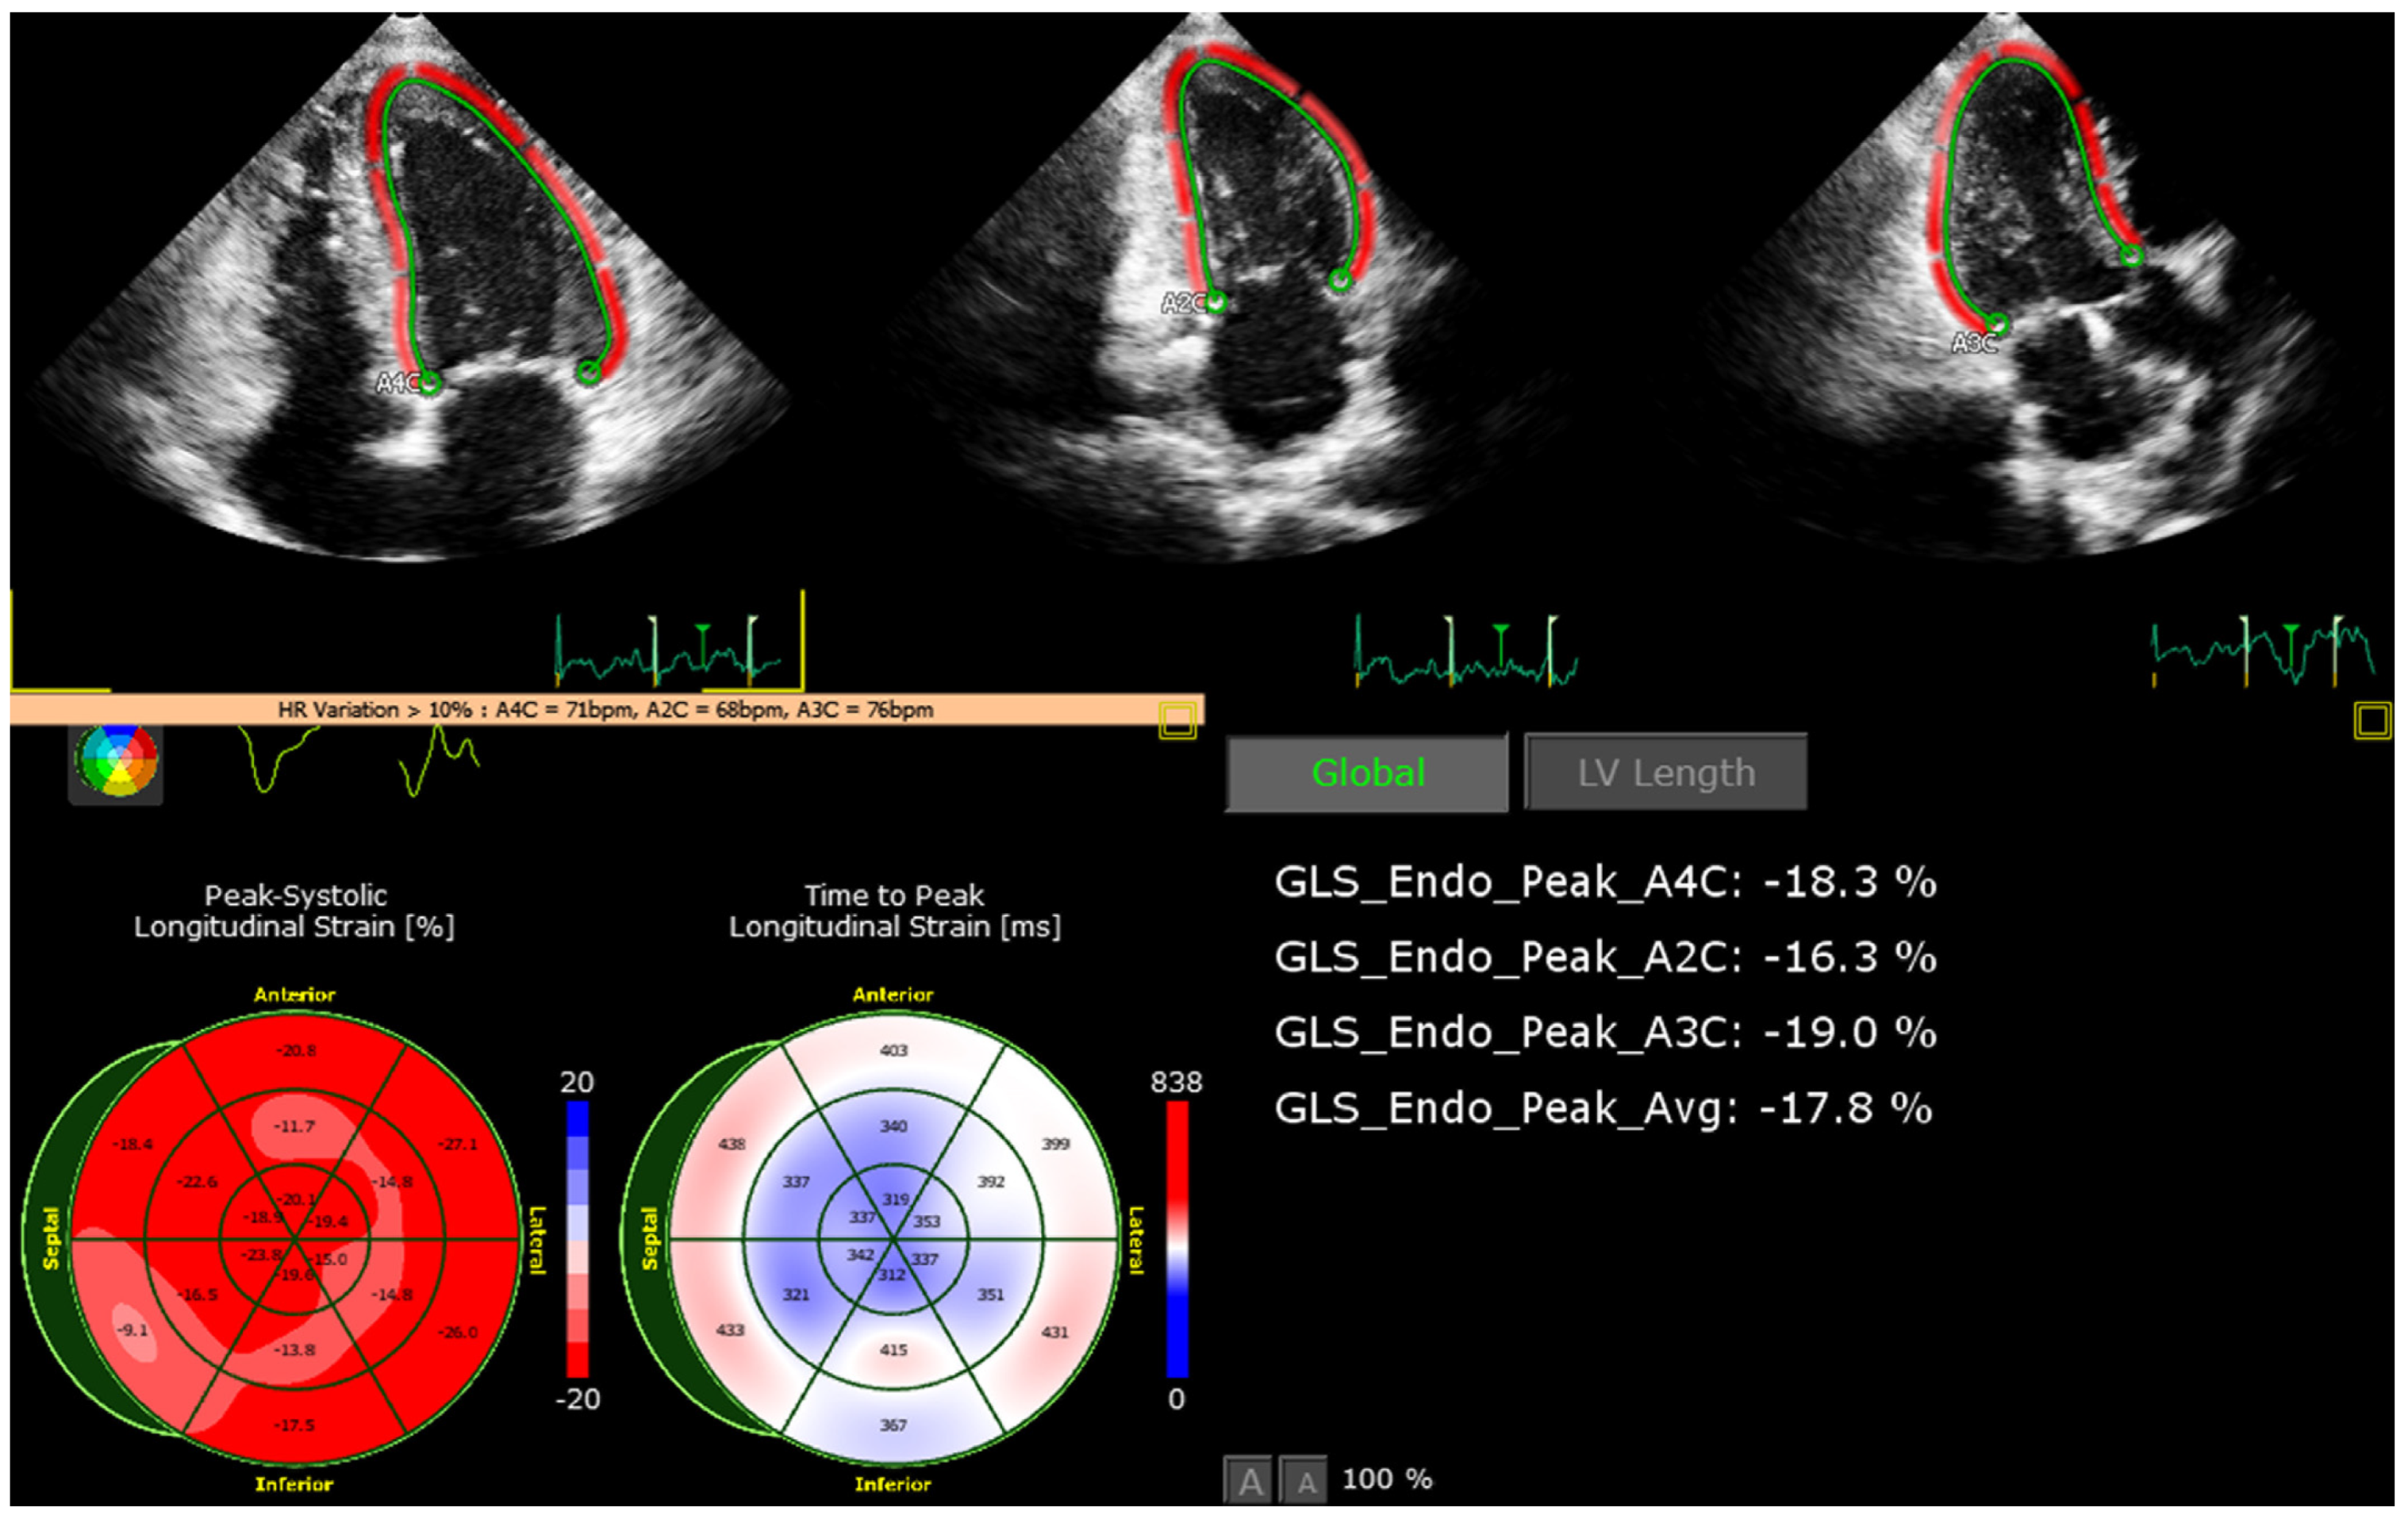

2.4. Investigations